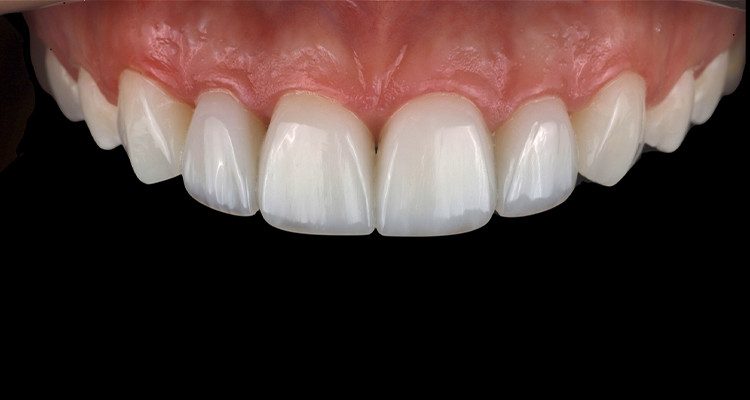

11 | Aspecto final das restaurações após acabamento e polimento.

Ao planejar o caso, foi constatado que a proporção estética ideal, entre altura e largura dos incisivos centrais, não seria possível sem incluir uma cirurgia periodontal de recontorno gengival, a qual a paciente optou por não realizar. Foi proposta como alternativa a inclusão de facetas nos caninos, para assim distribuir os acréscimos de resina de forma a obter um resultado mais agradável esteticamente. A paciente aprovou e o tratamento foi iniciado. A partir da remoção parcial das restaurações prévias, demostrando diferença nos formatos dos dentes remanescentes e manchas hipoplásicas nos centrais